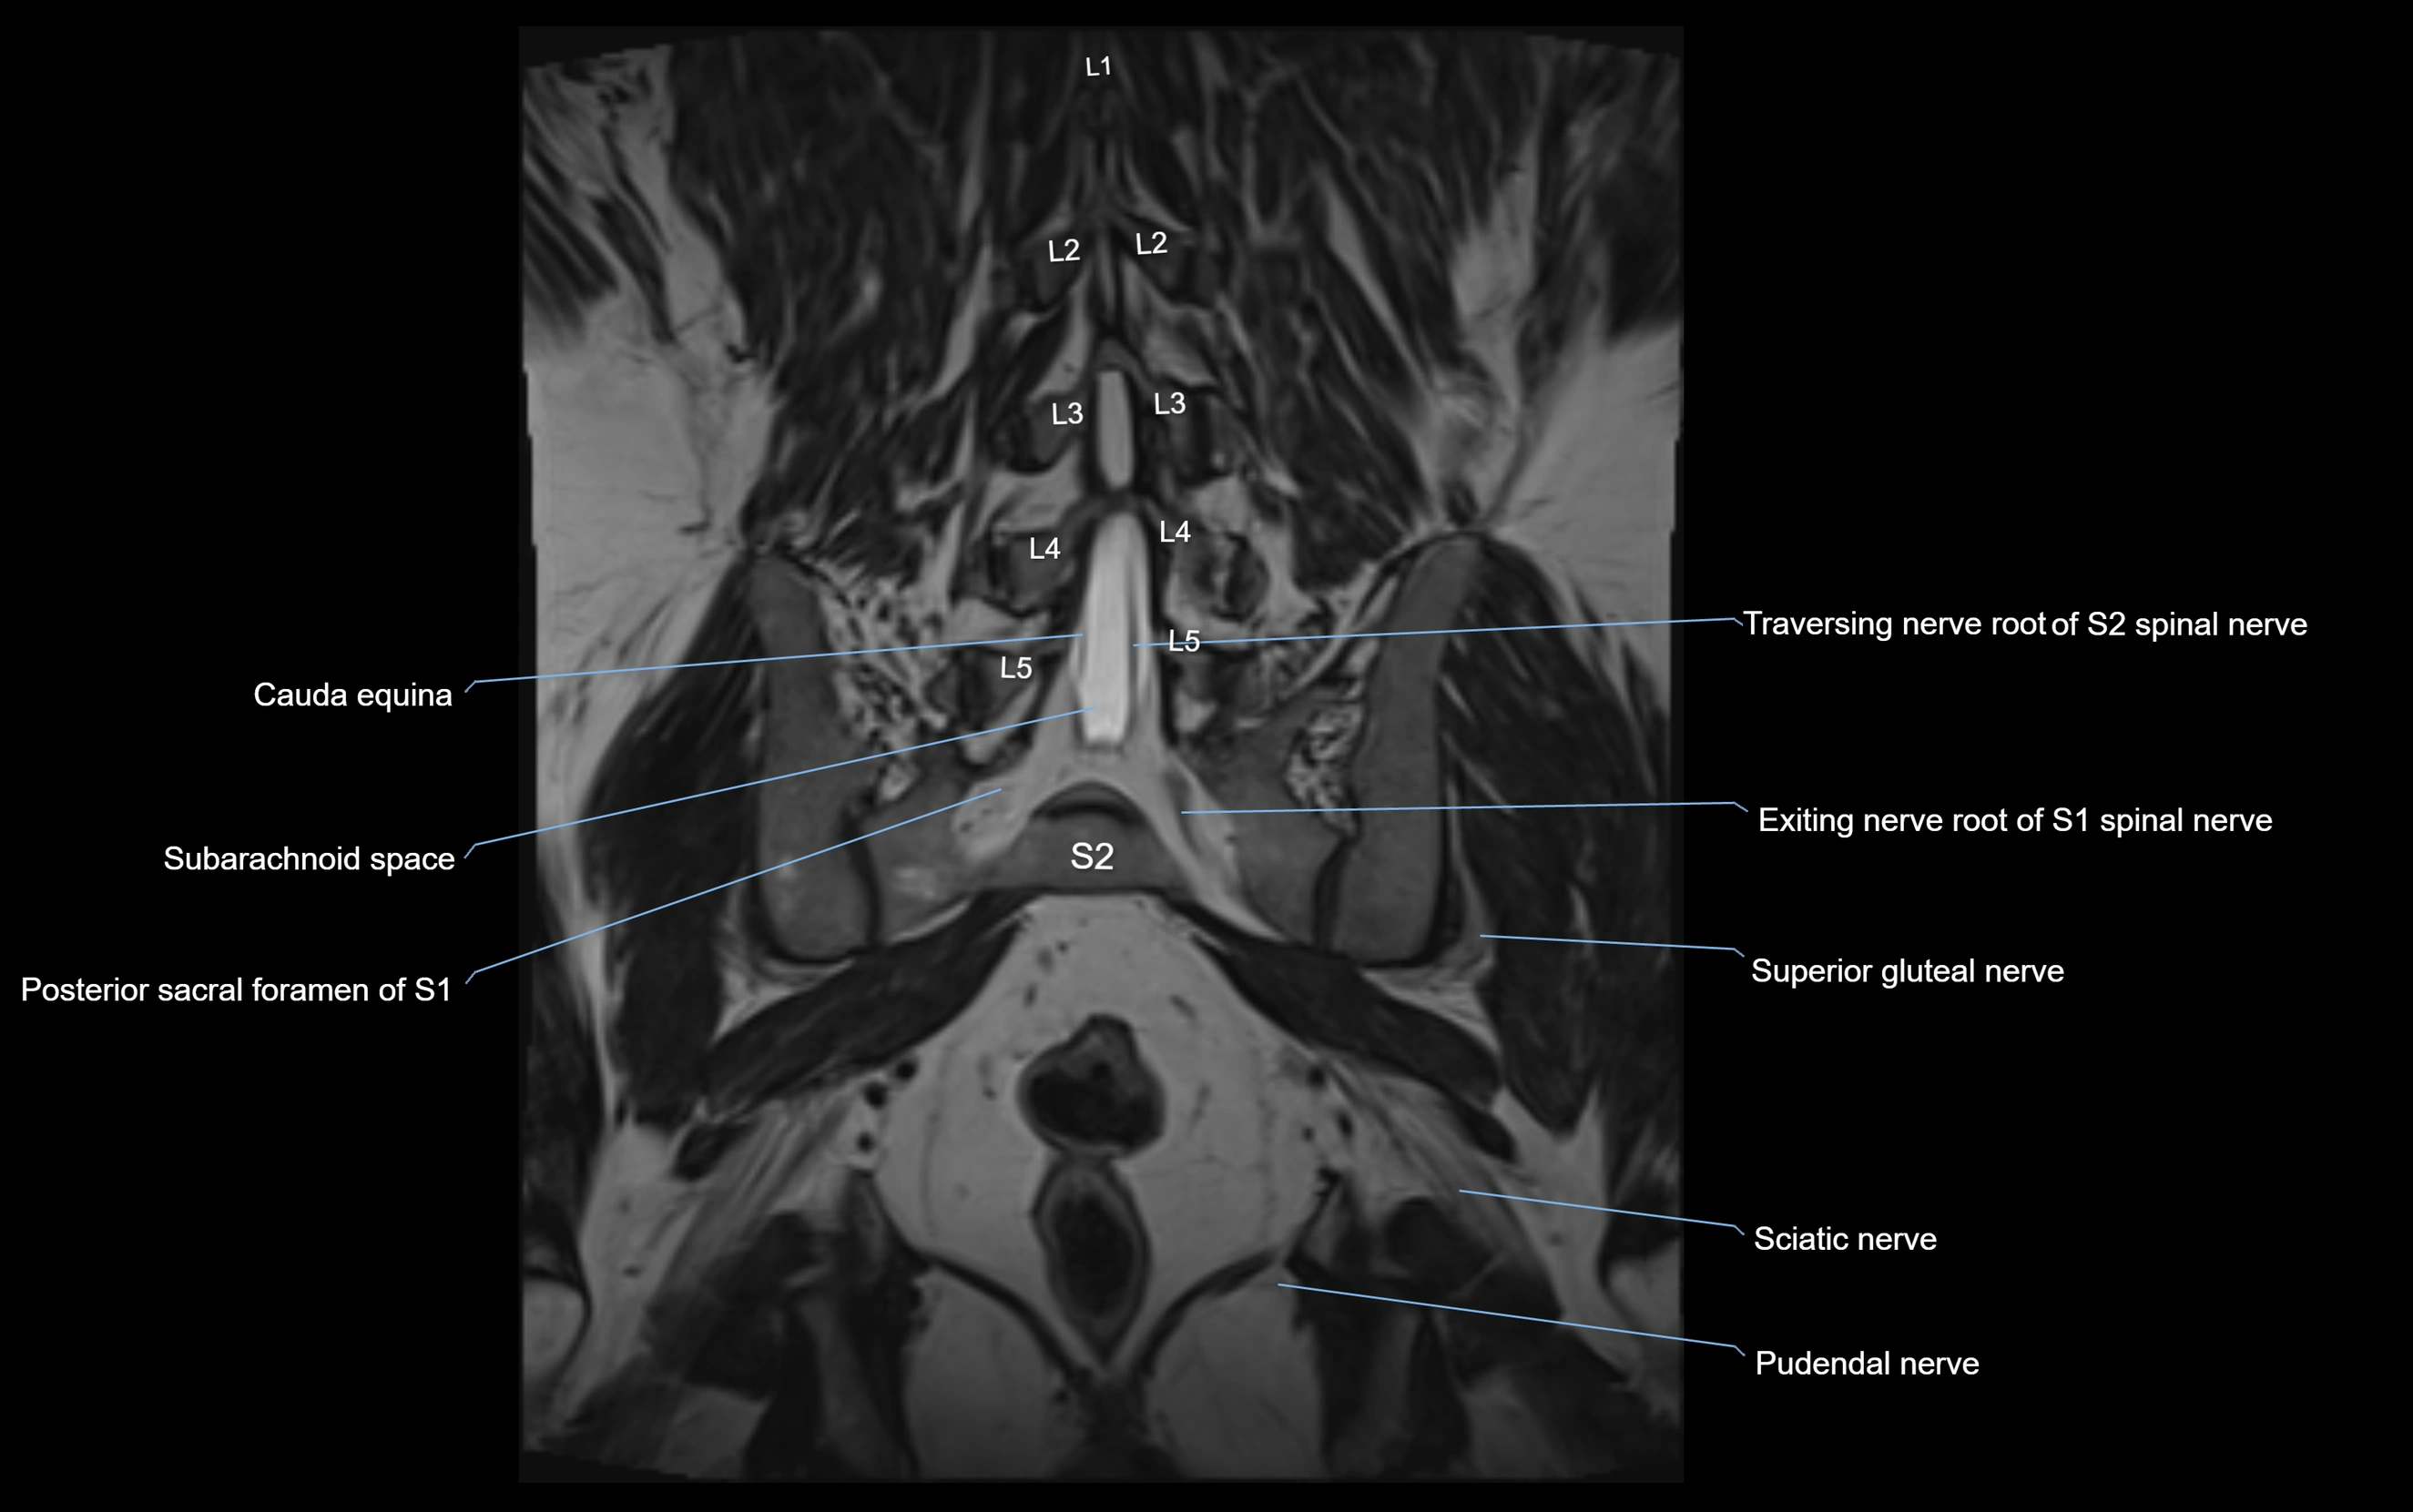

MRI Appearance

T1-weighted images:

• Nerve appears as a very thin low-to-intermediate signal intensity structure

• Surrounded by bright fat, aiding visualization

T2-weighted images:

• Nerve shows intermediate to mildly hyperintense signal compared to muscle

• Pathological involvement appears brighter

STIR (Short Tau Inversion Recovery):

• Normal nerve appears dark

• Inflamed or entrapped nerve appears bright hyperintense

T1 Fat-Sat Post-Contrast:

• Normal nerve enhances minimally

• Pathologic nerve (neuritis, entrapment, tumor infiltration) shows focal or diffuse enhancement

3D T2 SPACE / CISS:

• Nerve appears intermediate to mildly hyperintense compared to muscle

• Surrounded by bright fat or CSF, improving visualization

• Best sequence for mapping small pelvic nerves such as the anococcygeal